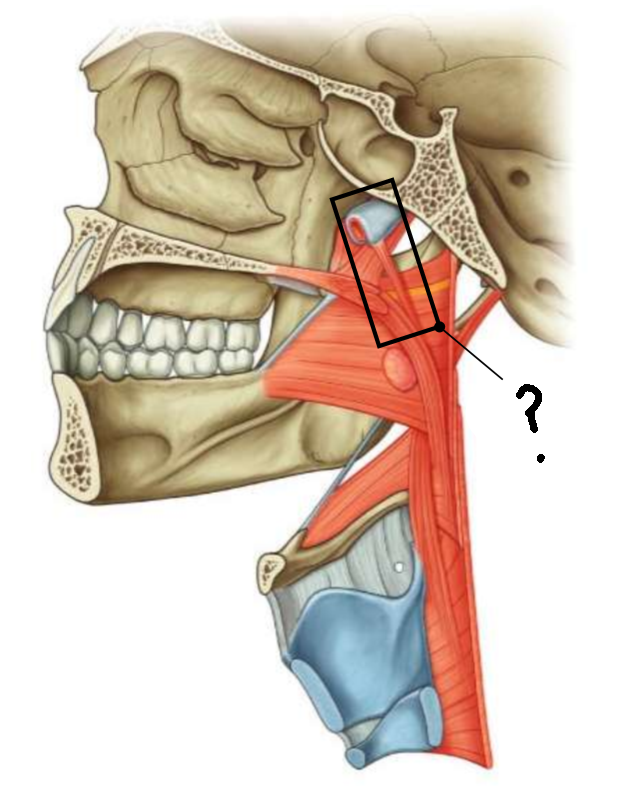

What muscle is this?

inferior constrictor

Which part of the muscle is 1?

thyropharyngeus

Which part of the muscle is 2?

cricopharyngeus

What are the attachments of this muscle?

oblique line of thyroid cartilage, cricothyroid tendon, cricoid cartilage → pharyngeal raphe

What is in the rectangle?

pharyngeal raphe

What is in the circle?

killians dehiscence

What is in the rectangle?

pterygomandibular raphe